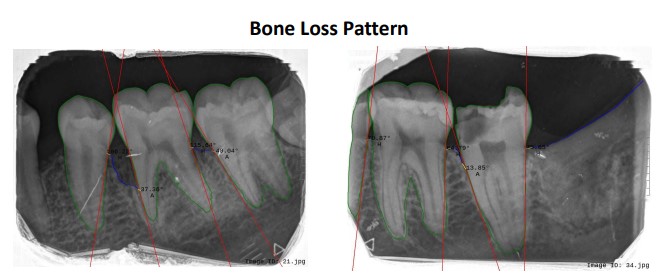

Using AI in determining alveolar bone loss in Dental X-rays to aid in periodontal diagnosis